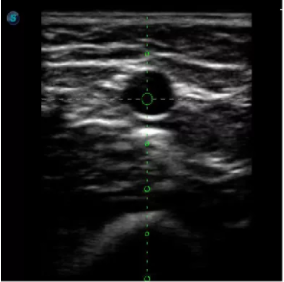

傳統(tǒng)腔內探頭采用直柄設計,在搭配穿刺架使用時,手術空間小,不易操作;生殖專用的曲柄探頭,探頭柄采用彎曲成角度設計,可實現(xiàn)監(jiān)視、取卵兩不誤,搭載穿刺架時,可以清晰顯示穿刺針的進針過程、深度和位置,實時監(jiān)視取卵全過程,保障取卵操作精準與安全。

取卵臨床圖